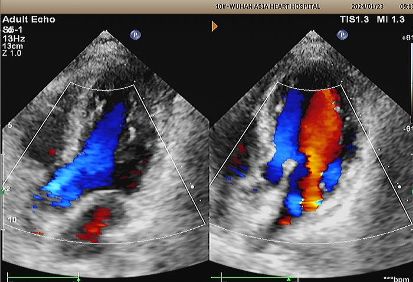

Diagnosis: Positive bubble study.

Implant: 2424 MemoSorb® biodegradable PFO occluder deployed under echo and DSA guidance.